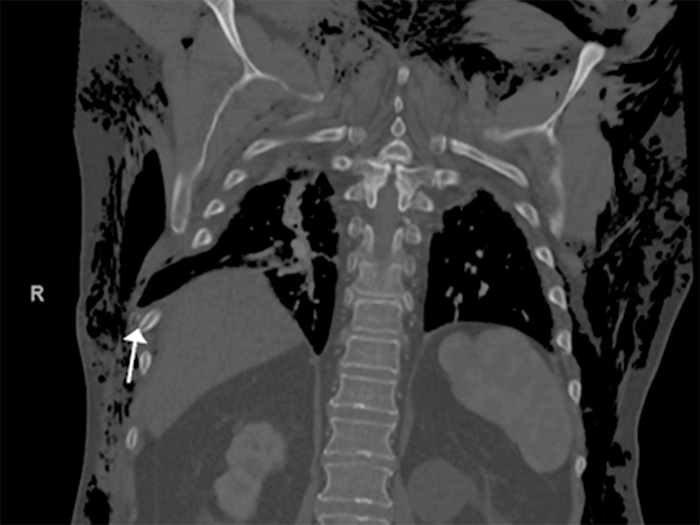

On arrival at our hospital, the patient had severe subcutaneous emphysema. She was hemodynamically normal, saturating 95% on a 3 L nasal cannula. Her imaging revealed comminuted and displaced fractures of right-sided ribs 7 through 9 (Figures 1, 2, and 3).

Figure 3. Comminuted Right Posterior 9th Rib Fracture (white arrow). Published with Permission